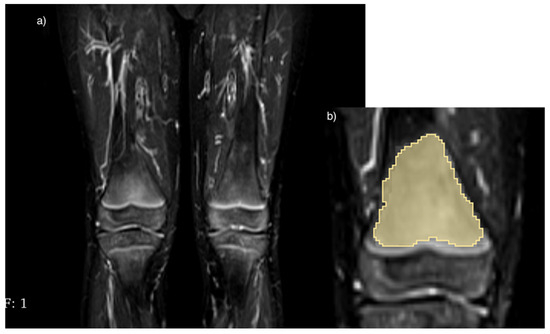

2.3. Processing of Images and Extraction of Features

- von Brandis, E.; Jenssen, H.B.; Avenarius, D.F.M.; Bjørnerud, A.; Flatø, B.; Tomterstad, A.H.; Lilleby, V.; Rosendahl, K.; Sakinis, T.; Zadig, P.K.K.; et al. Automated segmentation of magnetic resonance bone marrow signal: A feasibility study. Pediatr. Radiol. 2022, 52, 1104–1114. [Google Scholar] [CrossRef]